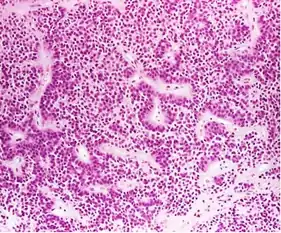

- Histological classification utilizes an immunohistological characterization of the tumors in terms of their hormone production.[47] Historically they were classed as either basophilic, acidophilic, or chromophobic on the basis of whether or not they took up the tinctorial stains hematoxylin and eosin. This classification has fallen into disuse, in favor of a classification based on what type of hormone is secreted by the tumor. Approximately 20-25% of adenomas do not secrete any readily identifiable active hormones ('non-functioning tumors') yet they are still sometimes referred to as 'chromophobic'.

Somatotroph pituitary adenoma, showing acidophilic cytoplasm A silent gonadotroph pituitary adenoma which is, in this case, is eosinophilic (contrary to normal, basophilic, gonadotroph cells)

A silent gonadotroph pituitary adenoma which is, in this case, is eosinophilic (contrary to normal, basophilic, gonadotroph cells) True null cell adenomas are typically composed of uniform, mildly atypical cells with chromophobic cytoplasm. This case has papillary architecture similar to gonadotroph adenomas.[53]

True null cell adenomas are typically composed of uniform, mildly atypical cells with chromophobic cytoplasm. This case has papillary architecture similar to gonadotroph adenomas.[53]